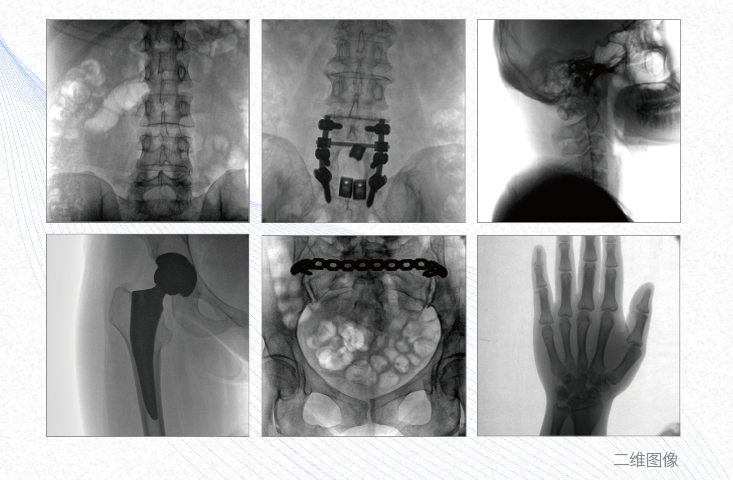

1、脊柱外科

有效重建復(fù)雜的脊柱三維模型,提供準(zhǔn)確的二維、三維圖像,提高螺釘植入的準(zhǔn)確性,縮短手術(shù)時間,減少并發(fā)癥的概率,降低輻射的攝入。

2、創(chuàng)傷外科

例如骨盆骨折內(nèi)固定術(shù),可術(shù)中三維重建髖臼關(guān)節(jié)面,準(zhǔn)確定位并植入螺釘,有效縮短螺釘植入的時間和透視暴露時間,減少術(shù)中及術(shù)后并發(fā)癥發(fā)生的概率。

3、關(guān)節(jié)外科

主要應(yīng)用于肩關(guān)節(jié)、肘關(guān)節(jié)、髖關(guān)節(jié)、膝關(guān)節(jié)的關(guān)節(jié)置換及解剖復(fù)位的定位。它可以準(zhǔn)確地置入假體,減少輻射時間,降低輻射劑量。

4、截骨矯形外科

例如治療先天性脊柱側(cè)后凸畸形,可有效引導(dǎo)術(shù)者植入后路螺釘并切除半錐體,達(dá)到滿意的截骨矯正效果。